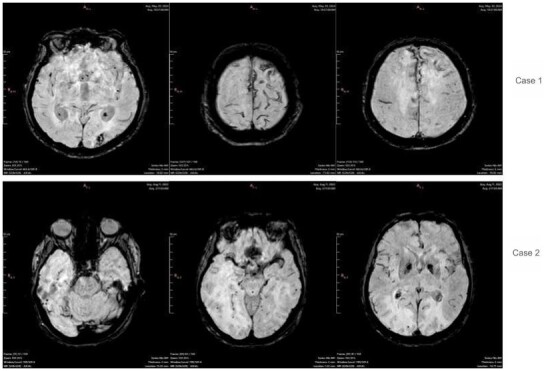

脑淀粉样血管病(CAA)是一种与β-淀粉样蛋白(a β)沉积在皮质和小脑膜血管相关的小血管疾病。传统上通过侵入性方法诊断,现在可以通过先进的成像模式来识别,提高了非侵入性诊断的准确性。一部分患者表现出炎症性表现,称为炎症性脑淀粉样血管病(CAA-RI),其特征是认知能力下降、行为改变和神经功能障碍。本研究重点介绍了两例CAA-RI,其亚急性发作,详细的临床进展,独特的MRI结果符合修订的诊断标准,能够早期怀疑。两例患者在免疫抑制治疗后均有显著改善,这加强了CAA-RI的潜在可逆性和早期识别的重要性。这篇文章强调了先进的影像学在CAA鉴别诊断中的重要性,以及通过及时治疗改善患者预后的潜力。

Cerebral Amyloid Angiopathy (CAA) is a small vessel disease associated with β-amyloid (Aβ) deposition in cortical and leptomeningeal vessels. Traditionally diagnosed through invasive methods, it can now be identified via advanced imaging modalities, enhancing non-invasive diagnostic accuracy. A subset of patients exhibits an inflammatory presentation, termed Inflammatory Cerebral Amyloid Angiopathy (CAA-RI), characterized by cognitive decline, behavioral changes, and neurological deficits. This study highlighted two cases of CAA-RI with subacute onset, detailed clinical progression, and distinct MRI findings consistent with revised diagnostic criteria, enabling early suspicion. Both cases showed significant improvement with immunosuppressive therapy, reinforcing the potentially reversible nature of CAA-RI and the importance of early recognition. This article underscores the relevance of advanced imaging in the differential diagnosis of CAA and the potential for improved patient outcomes with timely treatment.